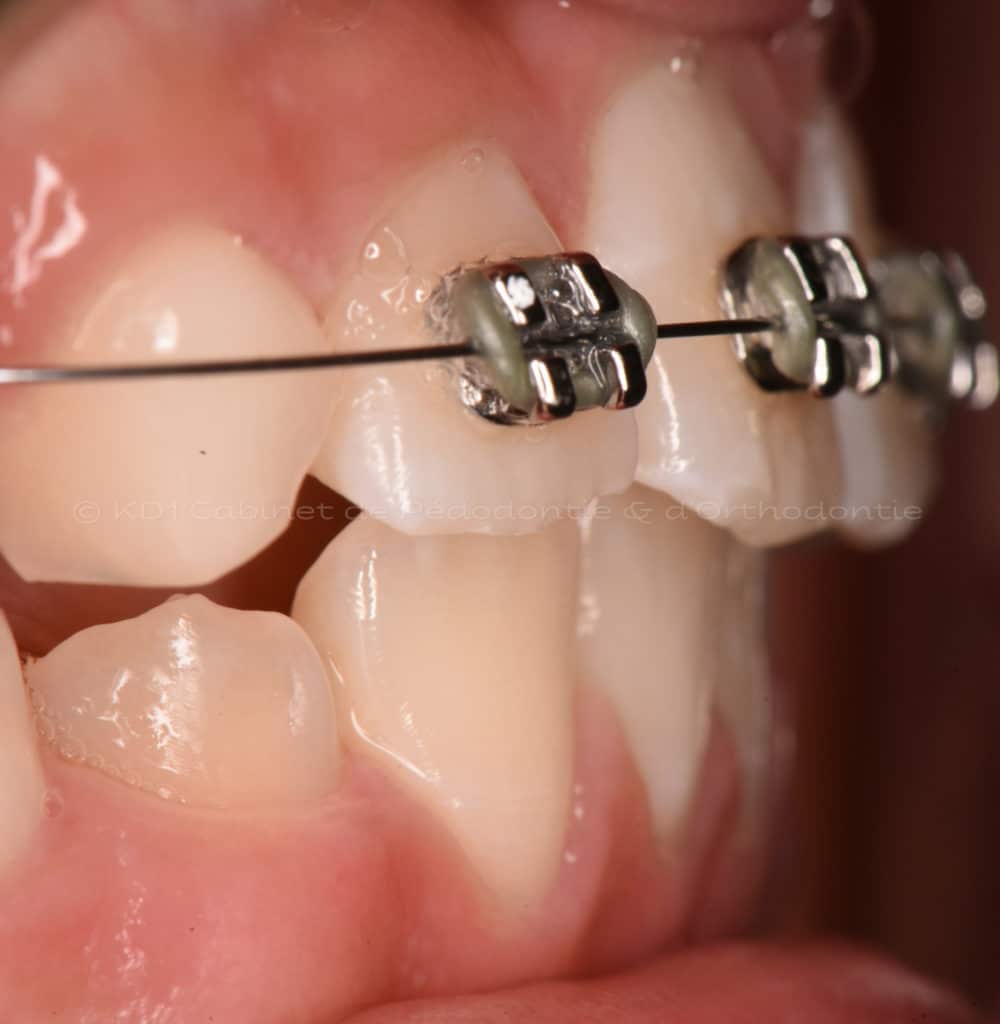

Cas #1 – Traitement avec des bagues, deuxièmes prémolaires et dent de sagesse supérieures ectopiques.